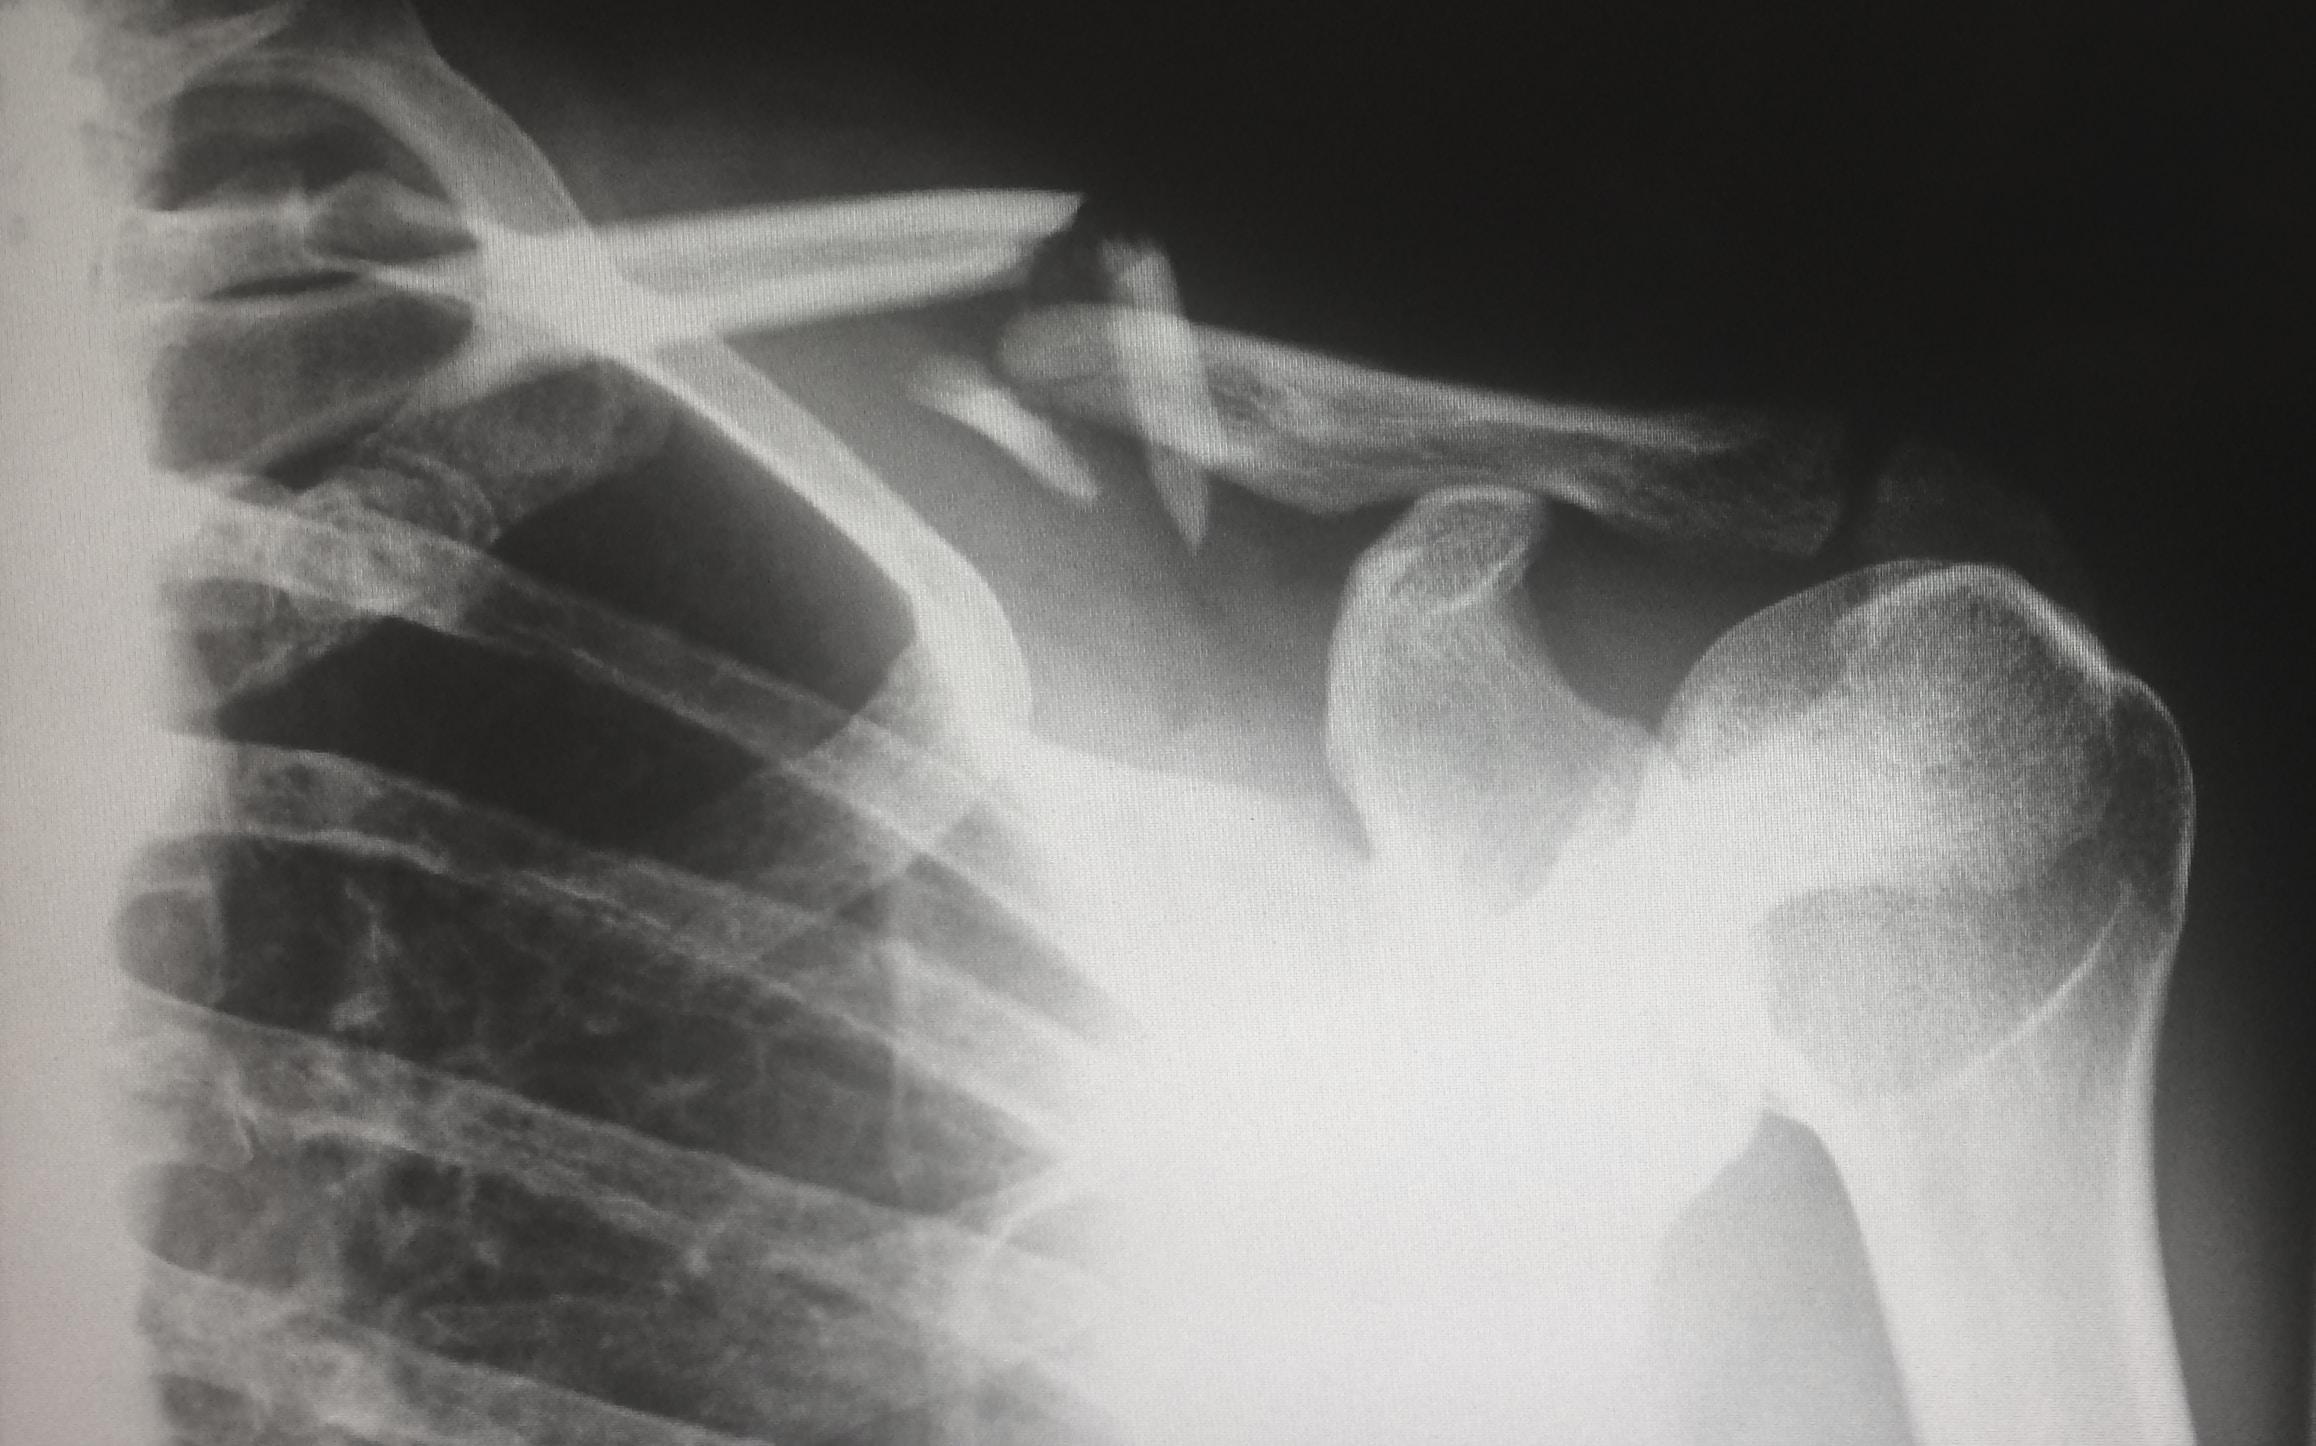

Zamrożony bark, znany również jako tzw. zespół zamrożonego barku lub przykotwicowe zapalenie kaletki, to dolegliwość związana z bólem i ograniczenie m ruchomości w stawie ramiennym. Stan ten może znacznie wpływać na codzienne czynności i jakość życia. W tym artykule omówimy przyczyny, objawy oraz metody leczenia i samopomocy w przypadku zamrożonego barku.